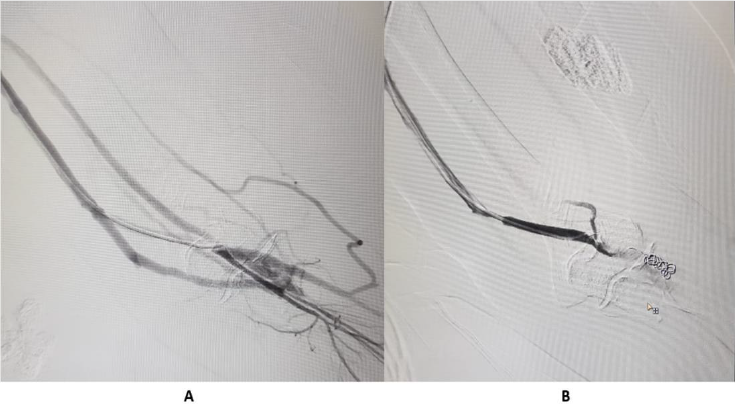

If right IJV is thrombosed, then IR accesses right External Jugular vein (EJV). If right side neck veins are thrombosed, then IR accesses left side neck veins: IJV or EJV (Figure 2). These tunnelled CVC are usually of size 14.5 French, with length 19, 23 or 27 cm, depending on patient’s height and from which side, neck vein is to be accessed. The cuff of tunnelled CVC is believed to prevent transmission of infection and also helps in securing CVC. If properly taken care of, then these tunnelled CVC can be used for 6-12 months. IR helps in managing these tunelled CVC, if flow rate is slow, by repositioning these CVC (Figure 3). IR have important role to play in managing AVF with slow flow rates. Most of times, stenosis is seen in these AVF, near anastomotic site. These juxta anastomotic AVF can be managed by IR by Percutaneous Transluminal Angioplasty (PTA), using appropriate size balloon. Some AVF show aneurysmal formation on venous side and these aneurysms can be managed successfully by IR (Figure 4). Sometimes, steal syndrome can be seen in AVF, due to reversal of flow in artery distal to anastomotic site. In case of steal syndrome, IR can block venous side using coils, in case of side to end AVF. This will increase flow rate in distal artery and reduce flow in fistula. In case of side-to-side AVF with steal syndrome, IR can successfully divert blood flow towards distal artery, by blocking collateral draining vein, distal to side-to-side anastomosis (Figure 5). If there is evidence of central vein stenosis, then IR can do PTA of central vein (Figure 6). If there is evidence of elastic recoil, with residual stenosis more than 30%, then IR can manage central vein stenosis by using metallic stent (Figure 7). Herein, it is important to stress upon Doppler and Spectral waveform, which helps IR to manage these dialysis fistula and graft [3-5]. In mature fistula and graft, inflow artery shows monophasic flow, with raised Peak systolic velocity (PSV) and End Diastolic velocity (EDV), with spectral broadening (Figure 8). In artery distal to anastomotic site, biphasic or triphasic waveform may be seen. On venous side, spectral waveform shows monophasic flow with turbulent arterial waveform (Figure 9).

Figure 5:

A. Steal syndrome, with collateral flow.

B. Coil emolization done, with improvement in arterial blood flow in distal forearm and wrist.